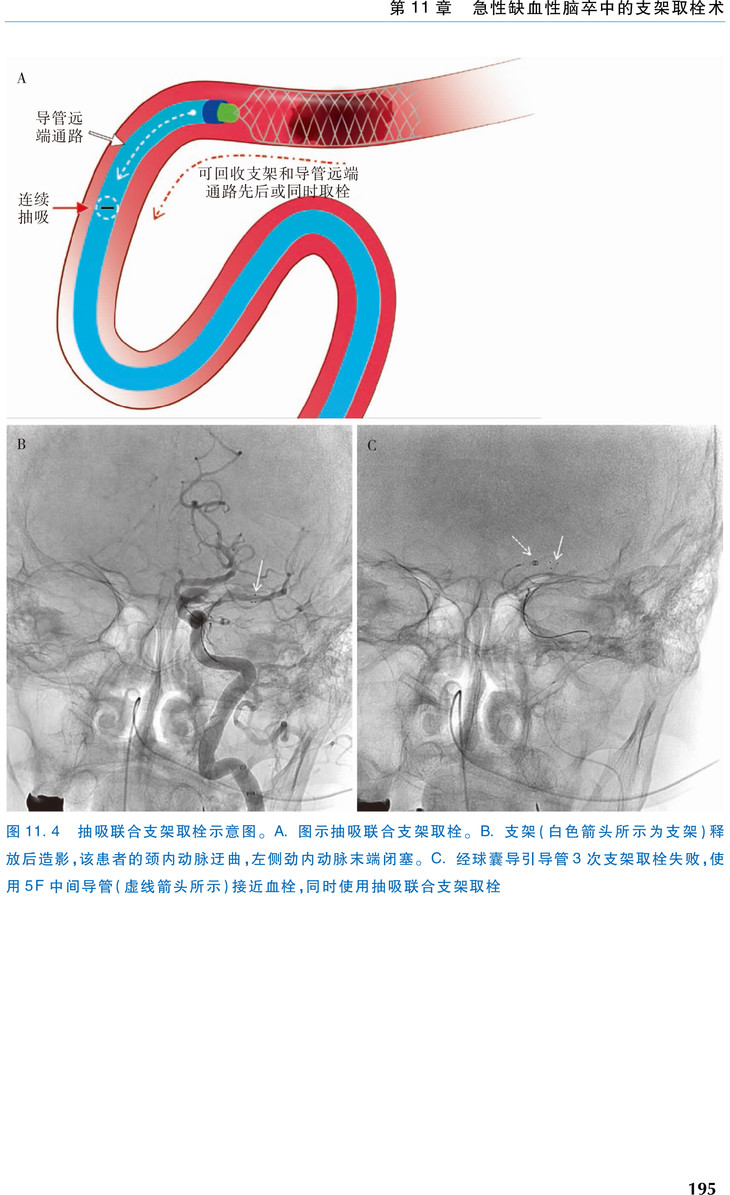

本书的主要内容:①缺血性脑卒中的病理生理机制和放射学诊断,重点介绍了烟雾病的病理生理学和机械取栓治疗颅内血栓的组织学特征。②药物治疗,例如静脉溶栓治疗。③介入治疗,包括抽吸取栓术和支架取栓术,以及支架取栓无效的难治性血管闭塞的病因和处理措施。④手术治疗,包括手术取栓、旁路手术和恶性大脑半球梗死的去骨瓣减压术。⑤卒中事件发生后患者的一般管理,重症监护,以及心脏评估与治疗。⑥儿童急性缺血性脑卒中的诊断和治疗。书中包含大量的影像学和手术图片,便于读者深入学习。